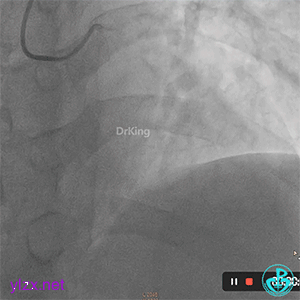

06 8天后复查冠脉造影

RCA粗大近中段瘤样扩张明显,中段血栓影消失,左室后支显影,后降支近段可见造影剂滞留, TIMI血流3-级。